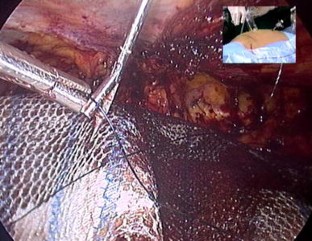

Fig. 1